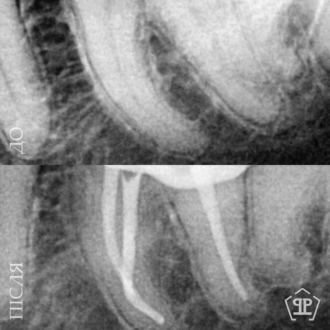

Перелечивание корневых каналов. Пациент обратился с признаками воспалительного процесса в верхнем зубе. Выявлены незапломбированные корневые каналы. Выполнен тщательное перелечивание с последующим герметическим пломбированием.